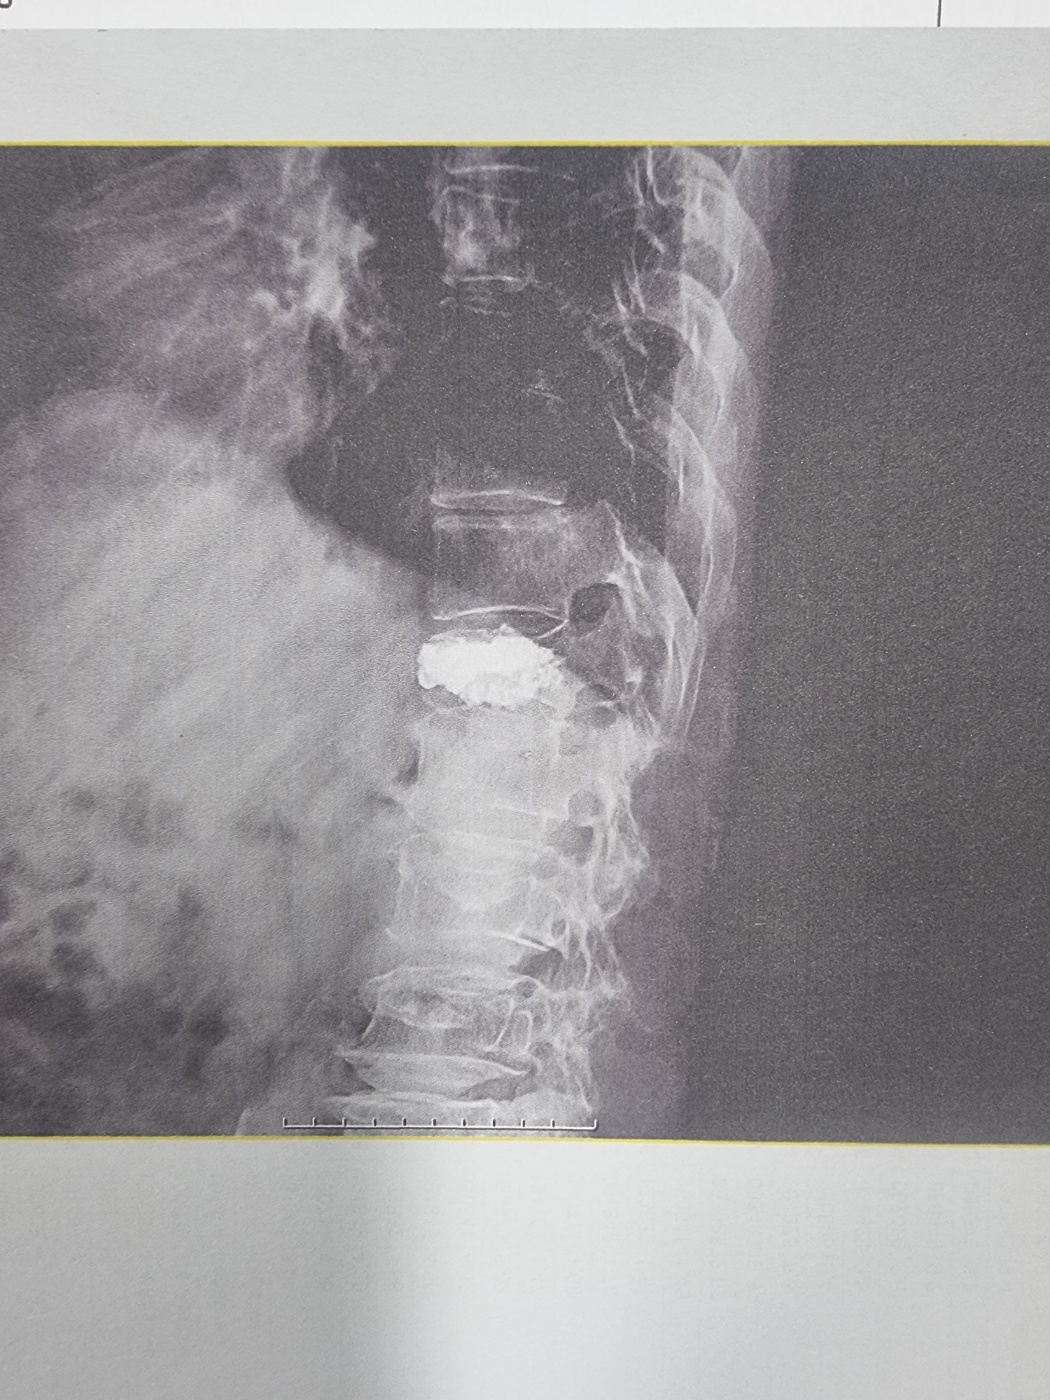

고객은 흉추 12번 압박골절 부위에 시멘트 삽입하는 척추 성형술 수술을 시행하였고, 이후 계속적인 치료후에도 방사선 검사상에 척추골절 압박정도가 심하여 압박율이 30%이상 되었습니다.